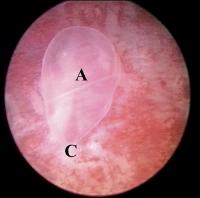

Thorakopagus

Abbildung 11: Embryoskopische Aufnahme eines Thorakopagus von 34 mm SSL, von rechts seitlich. Zwei separate Köpfe und eine ausgeprägte Verschmelzung am Thorax und im oberen Bereich des Abdomens, sind zu erkennen. (A) markiert Reste des Amnions (Karyotyp: 46,XX).